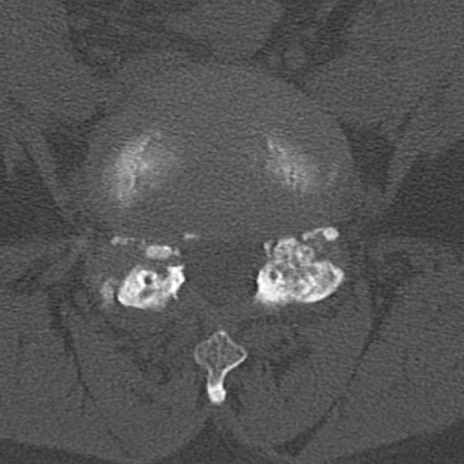

腰椎CT

横断像と矢状断像